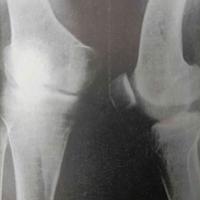

股骨下段及胫骨上段多数平行排列的横行致密

股骨下段及胫骨上段多数平行排列的横行致密线。膝关节外翻畸形。...